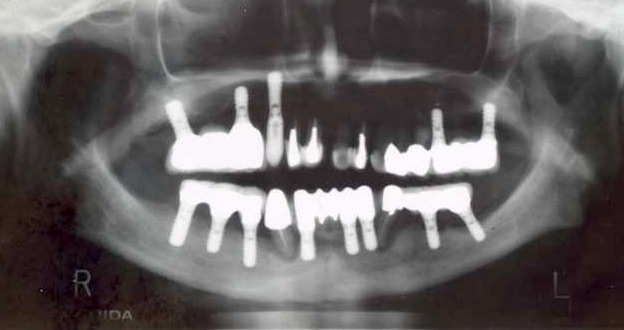

現在一番頭を悩ませている症例。

専門医は辞めたハズなのにこういう症例が

日々多いのです。

多分、手を付け始めたら半年は掛かるでしょう。

ありがちだけどあって欲しくない症例です。

結論と術式、費用はもう頭の中で出来上がってますが

この患者さんも1000万円近く治療費がかかった後なので

うーん、檜山が手をつけるか若しくは元のクリニックで

ちゃんと責任を取ってもらうか。

患者さんはもう戻りたくないとの事なので

やるしかないですね。

これも自称、世界一の某先生がやった症例です。